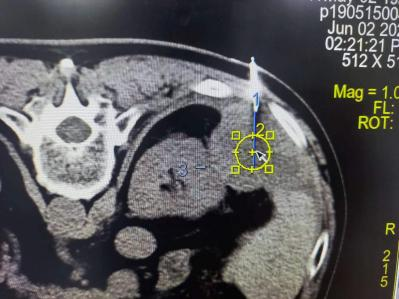

CT联合电磁导航设计穿刺点,穿刺路线及消融范围

术前由周筱燕副主任医师,王文杰主治医师,王倩主治医师介入射频消融团队通过仔细研究患者上腹部影像学检查,反复论证并详细化规划穿刺点、穿刺路线及消融范围。2023年6月2日进行CT联合电磁导航精准引导下肝恶性肿瘤射频消融术,该手术引导方式具有精准制导,避免多次穿刺,微创安全,手术时间短,出血少,并发症少,手术效果好等优点。术后患者恢复良好,未诉特殊不适。